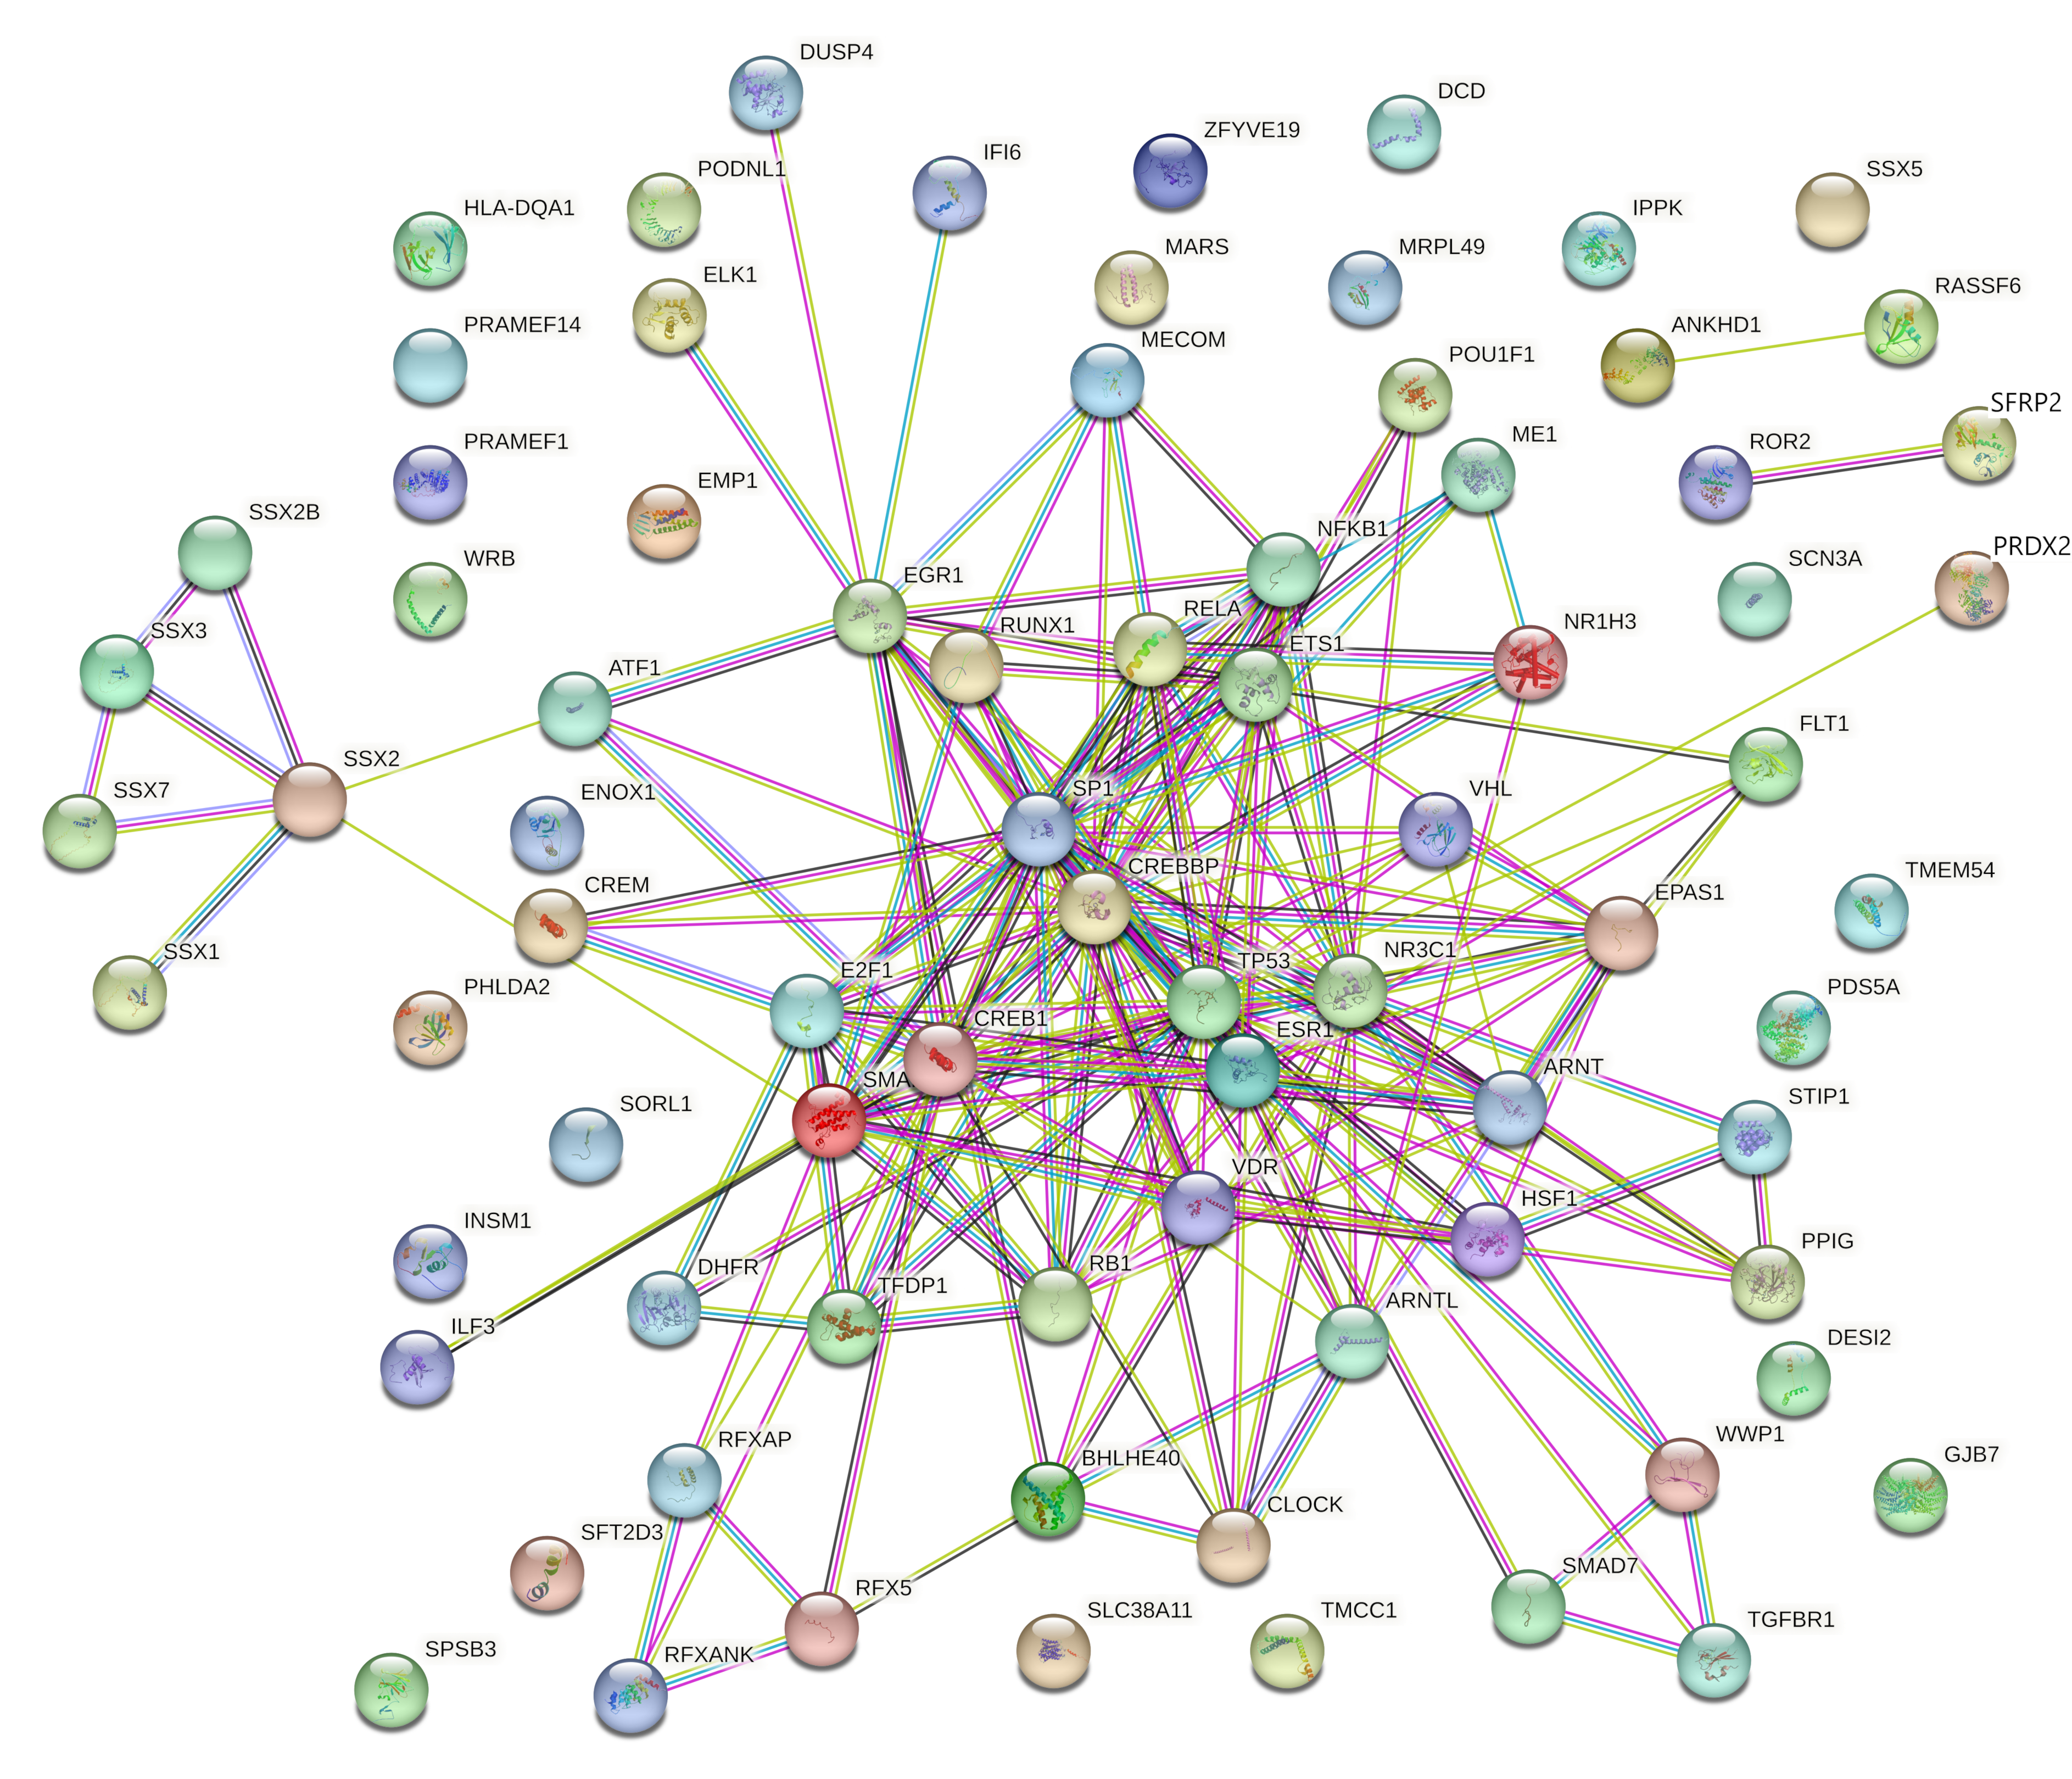

2.4.4. Identification and Analysis of Hub Gene

2.4.5. Gene Ontology and Functional Annotation Analysis of Hub Genes

3. Results

4. Discussion

4.4. Involvement of Hub Genes in Preeclampsia Development

4.5. Hub Genes with Diagnostic and Therapeutic Perspectives